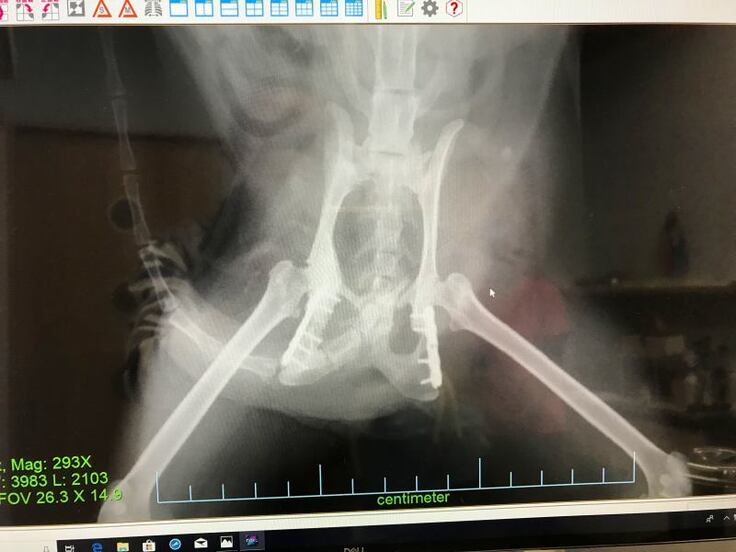

クロちゃん、目の瞬膜が時々出たままになっていたので治療と、骨盤の定期健診を受けてきました。

骨盤骨折手術を受けたところはまだ一部完全には繋がっていませんでしたが、

順調に回復しているということで…1年くらいしたら筋肉も着いて普通の猫と同じように走って高いところにもジャンプできるようになると思いますということでした。